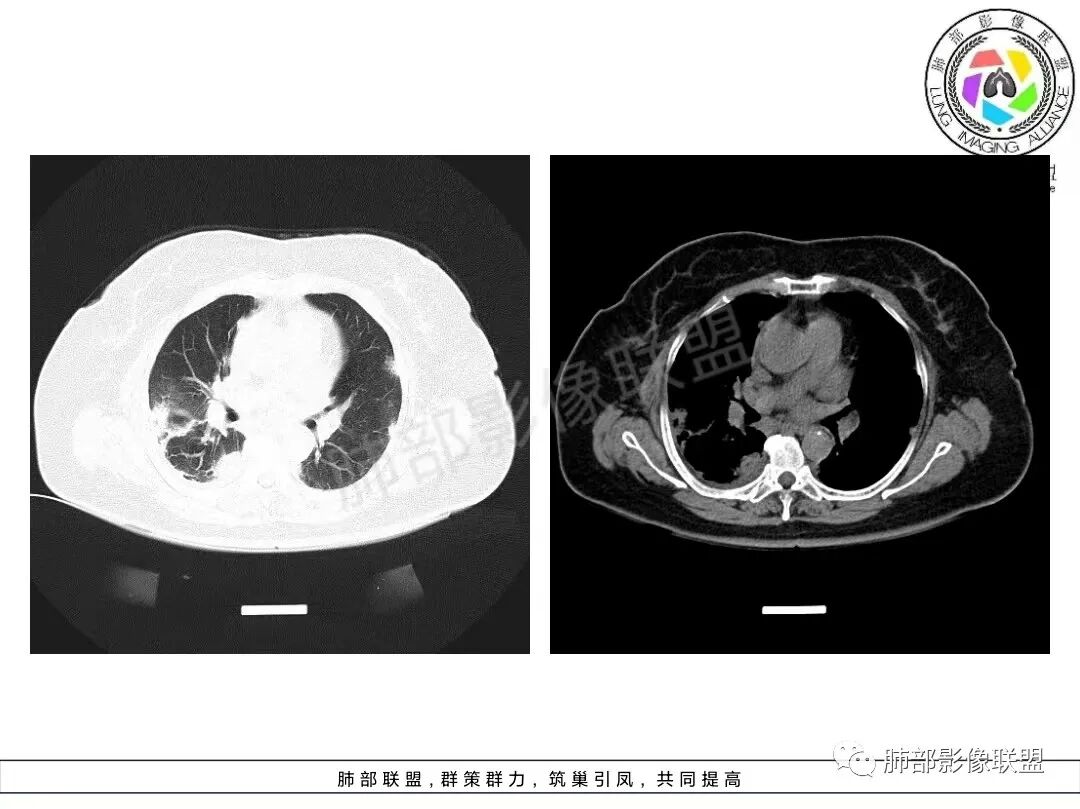

两肺沿胸膜下分布为主,大片、斑片状不均质实变,肺窗>纵隔窗,提示累及肺实质和间质,实变内充气支气管征空洞几乎不见,边缘收缩凹陷,部分平直,肺体积整体未见缩小。临床血氧降低,白细胞升高,考虑OP,COP,鉴别隐球菌,粘液腺癌!

老年女性,咳嗽、咳黄白痰,无发热,化验炎性指标高,右肺胸膜下实变,其内支气管充气、扩张,周围索条,左肺胸膜下多发结节及斑片实变,胸膜下线影,右侧少量胸水,考虑机化性肺炎,鉴别隐球菌、粘液腺癌

双肺胸膜下大片、斑片影,密度不均,边缘模糊,周围索条,右侧少量胸水,考虑机化性肺炎,鉴别隐球菌、粘液腺癌

老年女性,咳嗽、咳黄白痰,无发热,右肺胸膜下实变,其内支气管充气、扩张,周围索条,左肺胸膜下多发结节及斑片实变,胸膜下线影,右侧少量胸水,考虑机化性肺炎。

2、影像特点:双肺胸膜下为主、多发斑片影、结节样实变影及磨玻璃样密度影,大部分病灶边缘平直、边界清,磨玻璃密度病灶内可见细网格影,部分病灶内可见支气管扩张表现,部分支气管直达远端,部分中断于病灶中部。部分病灶有侧向融合趋势。